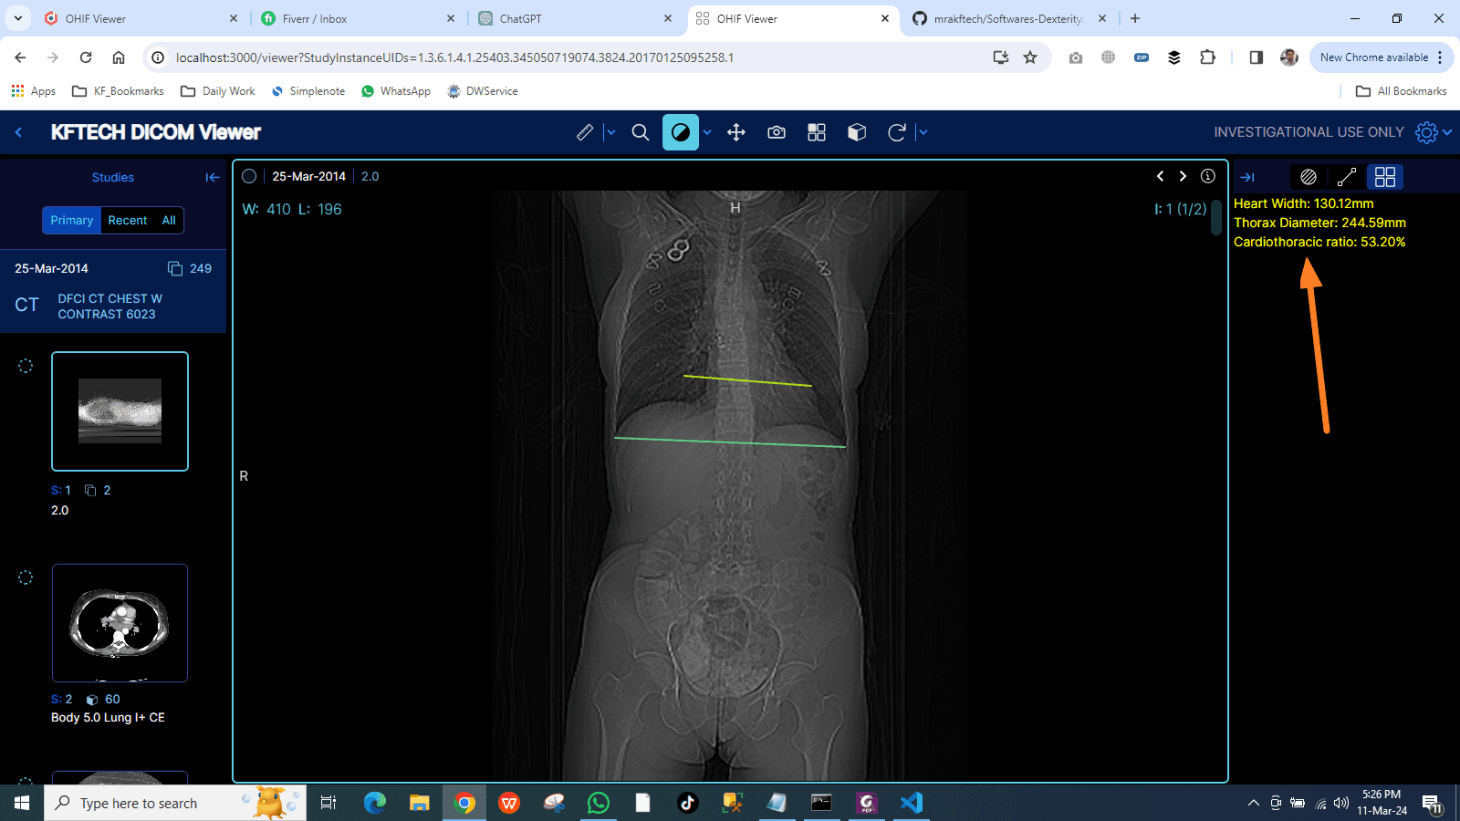

DICOM IMAGES VIEWER

The OHIF DICOM Viewer is a web-based medical imaging viewer designed to display and interpret DICOM (Digital Imaging and Communications in Medicine) images from various modalities such as X-ray, MRI, CT scans, etc.

It offers a user-friendly interface with advanced features for medical professionals to view, manipulate, and analyze medical images efficiently.

Key features includes :

multi-planar reconstruction, windowing, zooming, panning, measurement tools for distance and area calculations, annotations, image fusion, and support for 3D rendering.

The viewer is highly customizable and can be integrated with other healthcare systems, enabling seamless access to patient imaging data across different platforms.

Salient Feature

3D rendering and Multi-planer reconstruction.

Standard

Fully compliant with Healthcare standards.

Custom Development for OHIF Dicom Viewer

The OHIF DICOM Viewer is a web-based medical imaging viewer designed to display and interpret DICOM (Digital Imaging and Communications in Medicine) images from various modalities such as X-ray, MRI, CT scans, etc.

We offer custom development of Plugins, Extentions, Modes, ViewPorts for OHIF Viewer.

Our Development Strategy :

We listent carefully to our clients for their requirements or scope of work regarding new feature development for OHIF.

After deep analysis of requirements, We send Proposal with all details Cost, Delivery Time and Technical Specifications.

After discussion and final approval, and 50% Advance confirm payment from Client, We start Development and deliver successfully

Order Strategy

- Gather Requirements.

- Send Detailed Proposal.

- Start Development.

Extensions Types

- Tools Extensions.

- Reporting Extensions.

- Modes/ViewPorts.

DEV. Extensions

- CT Ration Finder.

- Speech Dictation.

- Reporting with Annotated Image and Measurements Auto Embedding.